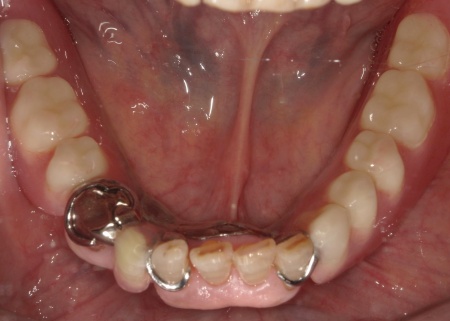

また、下顎は保険診療の部分入れ歯を再作製し、上下の噛み合わせの回復を図りました。

最後に、完成した入れ歯を装着し、噛み合わせや使用感に問題がないことを確認して、治療を終了しています。